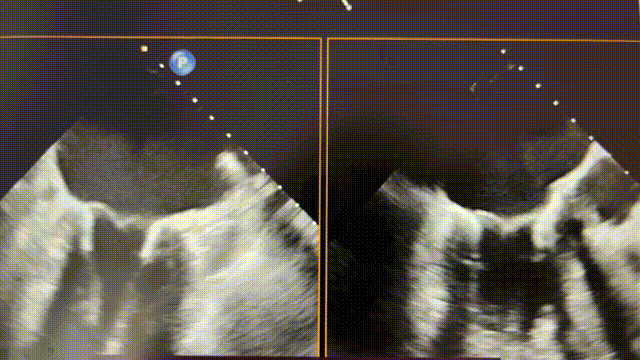

手术采用左侧第六肋间微创4cm切口心尖入路,在超声引导下,清晰识别MitraFix®输送系统准确跨瓣,并将人工瓣膜准确释放于二尖瓣瓣环,瓣膜释放后支架贴合牢固,术后无反流,二尖瓣前向血流通畅,左心室流出道通畅,流出道血流速度为1.2 m/s. 后顺利撤出输送系统,关闭心尖切口,手术顺利结束,手术skin-to-skin过程仅20分钟。